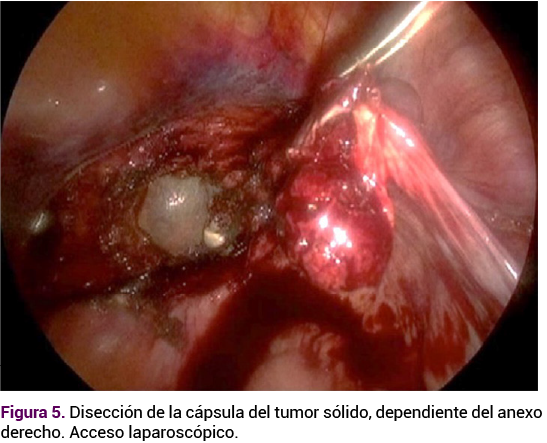

El caso se comentó con todos los integrantes del servicio y se decidió la laparoscopia con: histerectomía total con resección del tumor anexial. Durante la cirugía, en un primer tiempo, se efectuó la histerectomía, sin contratiempos. En el anexo derecho se apreció un tumor de 3 x 2 cm, de bordes bien definidos, móvil, con vasculatura superficial aumentada, sin focos de necrosis o sangrado. La apertura de la tumoración se hizo con corte frío y se encontró tejido friable. La escisión del tumor fue total, con aplicación de endo-loop en la base, con adecuada hemostasia y extracción del tumor por medio de una endobolsa.

Figura 5. Disección de la cápsula del tumor sólido, dependiente del anexo derecho. Acceso laparoscópico.